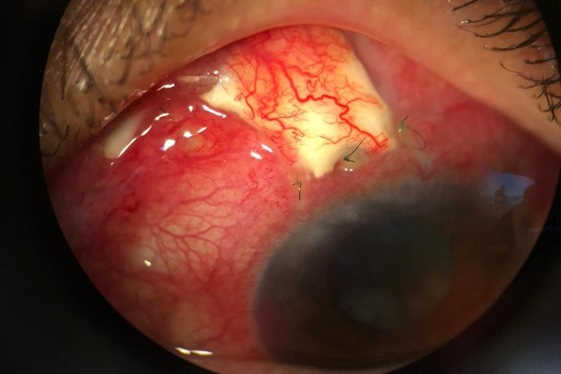

However, she returned after 10 days with a history of gritty sensation in the left eye and admitted to having rubbed it vigorously. Although the vision and IOP was maintained in the left eye, there was a retraction of the conjunctiva at the limbus, with broken sutures exposing the tube of the glaucoma implant. She was taken back to theatre where a very friable conjunctiva was sutured back. She continued with the same drops and at four-week follow-up presented with conjunctival erosion and an exposed tube of the glaucoma implant (Fig1). She maintained vision of 6/12 and IOP of 8mmHg in the left eye.

Fig 1. Conjunctival erosion with exposure of the tube of the Ahmed glaucoma valve implant